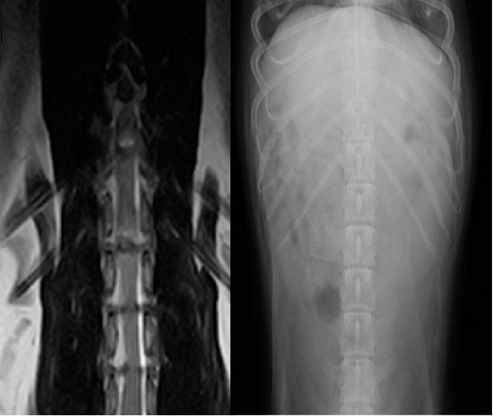

【画像診断】~ダックスフンド、雄10歳、グレート3の椎間板ヘルニア~

▲MRIのT2強調の矢状断面(キャミックに依頼)

▲椎間板ヘルニアがあるMRI像、冠状断像T13-L1の造影なしのT2強調画像、T2強調の矢状断面(キャミックに依頼)

▲ダックスフンド、病変部は胸椎T13-腰椎L1の単純X線検査像の側面像